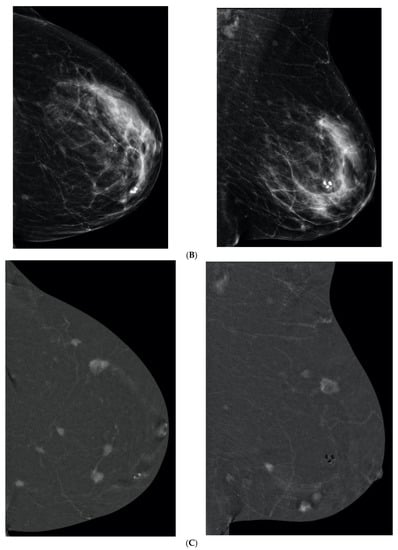

8. Contrast-Enhanced Mammography (CEM)